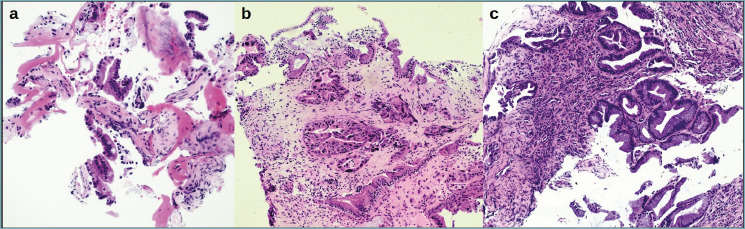

Methods: Twenty-two prospective patients were included, and submitted to ERPC-guided biopsy or biliary resection. By histopathological analysis plus fluorescence in situ hybridization (FISH) for chromosomes 3, 7, and 17 aneuploidies, 8 cases (36.4%) were malignant, and 14 cases (63.6%) were negative. NGS was performed on paraffin-embedded tissue by a laboratory-developed panel allowing the analysis of hot-spot regions in 28 genes. Digital PCR (dPCR) was performed by QuantStudio™ AbsoluteQ™ solid dPCR and the copy-number variation (CNV) of the chromosomes 3, 7, and 17 analysed.